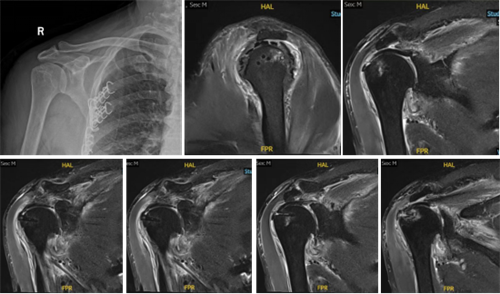

图1 术前影像学资料:69岁,男性,巨大不可修复性肩袖损伤;Hamada分型3型、Goutallier分级3级。